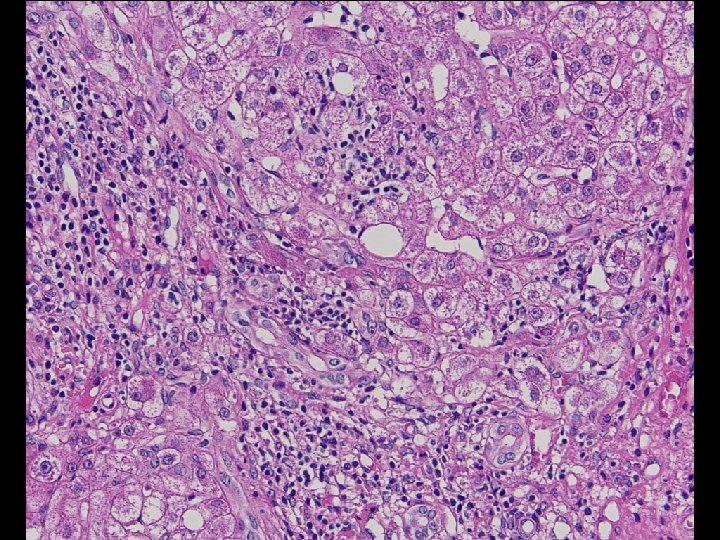

Diagnose einer NASH (Mindestkriterien) • Überwiegend makrovesikuläre, Läppchenzentren betreffende Steatose, die im Stadium der Zirrhose aber verschwinden kann; • Milde Infiltration des Leberparenchyms durch neutrophile Granulozyten und Rundzellen; • Ballonierung der Hepatozyten.

Zusatz-Kriterien für NASH • • • Mallory-Hyalin Glykogen-Lochkerne Perisinusoidale Fibrose der Zone 3 Megamitochondrien (Adoleszenten) portale lymphozytäre Entzündung.

Tabelle 3. NASH Clinical Research Network Scoring System (I) NASH-Aktivitäts-Score (NAS) Grad der Steatosis Lobuläre Entzündung Hepatozytäre Ballonierung 0: <5% 0: Keine 1: 5 -33% 1: 2 Foci/20 x. Feld 1: Leicht, wenige Zellen 2: 34 -66% 2: 2 -4 Foci/20 x. Feld 2: Mäßig – stark, viele Zellen 3: >66% 3: > 4 Foci/20 x. Feld NAFLD Aktivitäts-Score (NAS): 0 -8 Steatose (0 -3) + Lobuläre Entzündung (0 -3) + Ballonierung (0 -2) < 3 = keine NASH, ≥ 5 = sichere NASH